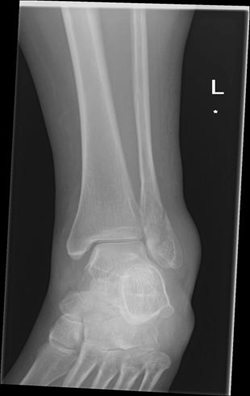

A 43-year-old female marathon runner presented with a stress fracture in the distal region of the fibula. She had been experiencing pain in her ankle for several weeks, and the pain had worsened recently. She was unable to run or walk without pain. The patient did not have any underlying osteometabolic pathologies and used an intrauterine device for contraception. She also underwent regular nutritional monitoring and maintained an adequate sleep schedule, which is crucial for bone health and overall recovery. X-rays and MRI confirmed the presence of a stress fracture.

The MRI showed significant edema and a clear fracture line in the distal fibula. Initially, she was placed in a walking boot and instructed to rest her leg, reducing weight-bearing activities to allow the bone to heal. After four weeks of rest, her pain had improved, but the fracture was not yet fully healed, as indicated by follow-up imaging. Given her active lifestyle and the need for a quicker recovery, the patient was started on teriparatide 20 mcg daily.

Her recovery was marked by a steady improvement in pain levels and functional outcomes, allowing her to resume her athletic activities with confidence. (Figure 1,2)

Figure 1 MRI of Fibula with Fracture: A case of a distal fibula fracture showing a mildly displaced oblique fracture at the level of the syndesmosis.